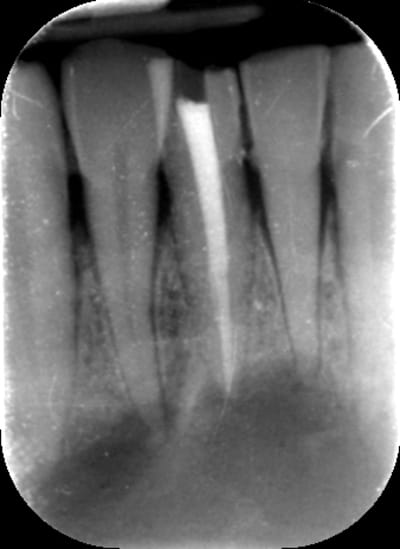

Si bien entendu endo faite après séance CaOH à J-7 et obturation à J-2.

#1 - As tu réalisé une obturation à retro ?

> #1 - As tu réalisé une obturation à retro ?

Non je ne pense pas que cela soit indispensable

Le but de ma question était de savoir si on peut être sûr que l'obturation endo a été réalisée dans de bonnes conditions : taille gigantesque de lésion périapicale, 6 jours de Ca(OH)2, risque de suintement lors de l'obturation ?

Si j'avais dû traiter ce cas, je pense que j'aurais fait une obturation à rétro pour minimiser le moindre risque.

je suis pas expert en endo, mais je vais donner mon avis ( qui est celui de stéphane aussi il me semble ), une obturation à retro non si l'endo a été faite dans les règles de l'art, mais par contre si tu as un doute tu peux faire une résection apicale.

vu que l'endo est récente et faite en principe dans les règles de l'art, l'obturation à rétro n'a pas d'intérêt dans ce cas.

comme le dit mac, une simple résection apicale à minima permet d'éliminer la partie terminale qui comporte le delta apical dont certains canalicules ne sont pas forcément obturés correctement.